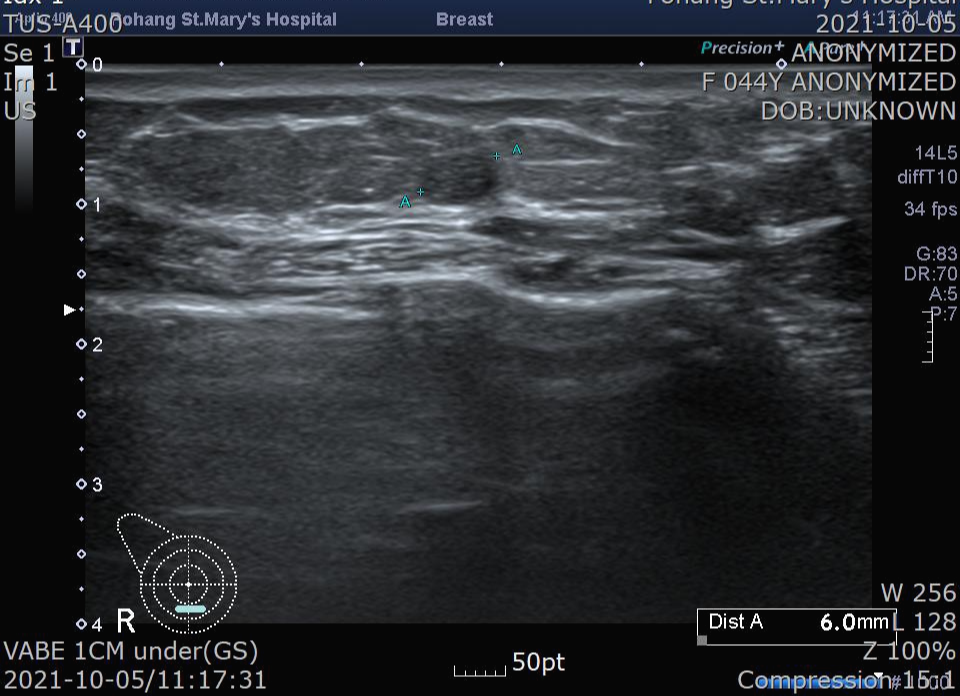

제가 직접 시술한 환자 사진을 보여드립니다.

44세 여자분이었습니다.

병변을 먼저 확인합니다.

종양주위에 국소마취를 진행합니다. 국소 마취할때가 통증이 좀 있고 마취가 잘되고 나면 통증은 거의 사라집니다.

맘모톰 칼날이 종양 바로 아래에 위치하게 합니다. 진공(음압)을 걸고 칼날을 열어주면 위 그림과 같이 됩니다. 칼날이 열린 부분을 화살표로 표시했습니다.